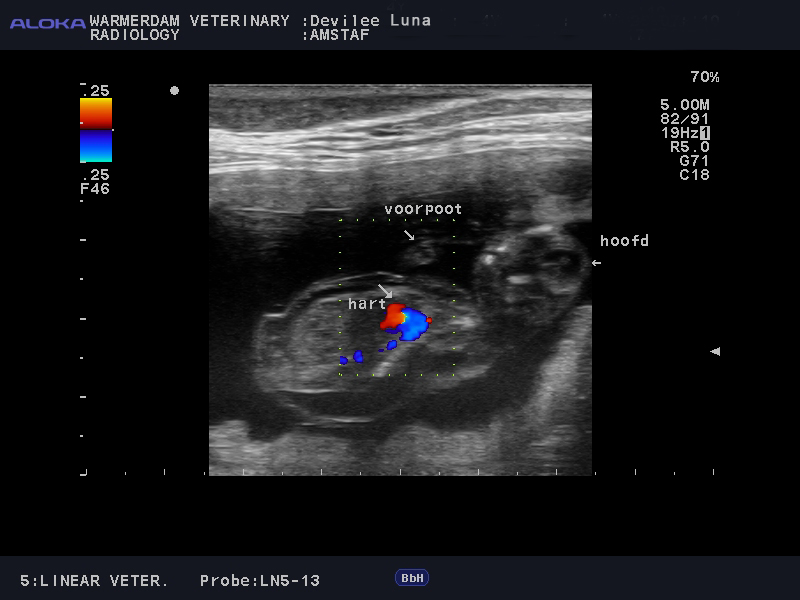

Echo

Vandaag hadden we de geplande echo van Luna. De auto rit er naartoe werkte niet mee, er bleek een ongeluk gebeurd te zijn waardoor we ruim 45 min vertraagd waren. We keken al zo erg uit naar deze dag en nu duurder het alleen maar nog langer hahaha. Eindenlijk aangekomen moesten we nog een geruime tijd wachten omdat we tussendoor ingepland werden. Het lange wachten was niet voor niks, we kunnen met veel trots aankondigen dat Luna drachtig is!! We zijn zo blij wand we keken al ruim een jaar uit naar deze mooie combinatie. De pups zullen eind Juli verwacht worden.